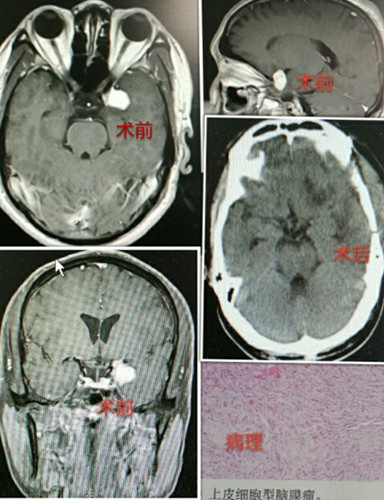

48岁的男性患者高某,10月18日入院神经外科二病区,其家人告知此患者已出现发作性意识障碍3月,入院后行颅脑CT及MR提示:左侧颞部蝶骨脑膜瘤。入院后白西民主任医师高度重视,积极进行术前准备及讨论,反复与患者家属沟通,家属要求在我院手术治疗。10月26日,由白西民主任医师主刀,杜春亮主治医师、赵云洁住院医师及手术麻醉科配合,在全麻下行鞍结节脑膜瘤切除术。通过大家的努力,在显微镜下成功全切除肿瘤。病理检查提示:上皮细胞型脑膜瘤。术后经过治疗及护理,患者目前恢复良好,已经痊愈出院。

鞍结节脑膜瘤,又称鞍上脑膜瘤,对起源于鞍结节、前床突、鞍膈和蝶骨平台的脑膜瘤统称。由于缺乏特异性的症状及体征,故不易早期发现,因此凡发现患者有进行性视力减退、单或双颞侧偏盲,伴有头痛,眼底有原发性视神经萎缩或Foster-Kennedy综合征者,即应考虑鞍结节脑膜瘤的可能性,确诊主要靠影像检查。CT、MRI的普及为此病诊断提供了简单易行、安全可靠的诊断手段。由于肿瘤毗邻视交叉、颈内动脉、前循环动脉、下丘脑、垂体柄等重要结构,手术难度大,术后并发症多,要求术者有准确的解剖和熟练的显微外科手术技术。本例患者肿瘤被全部切除,无并发症。